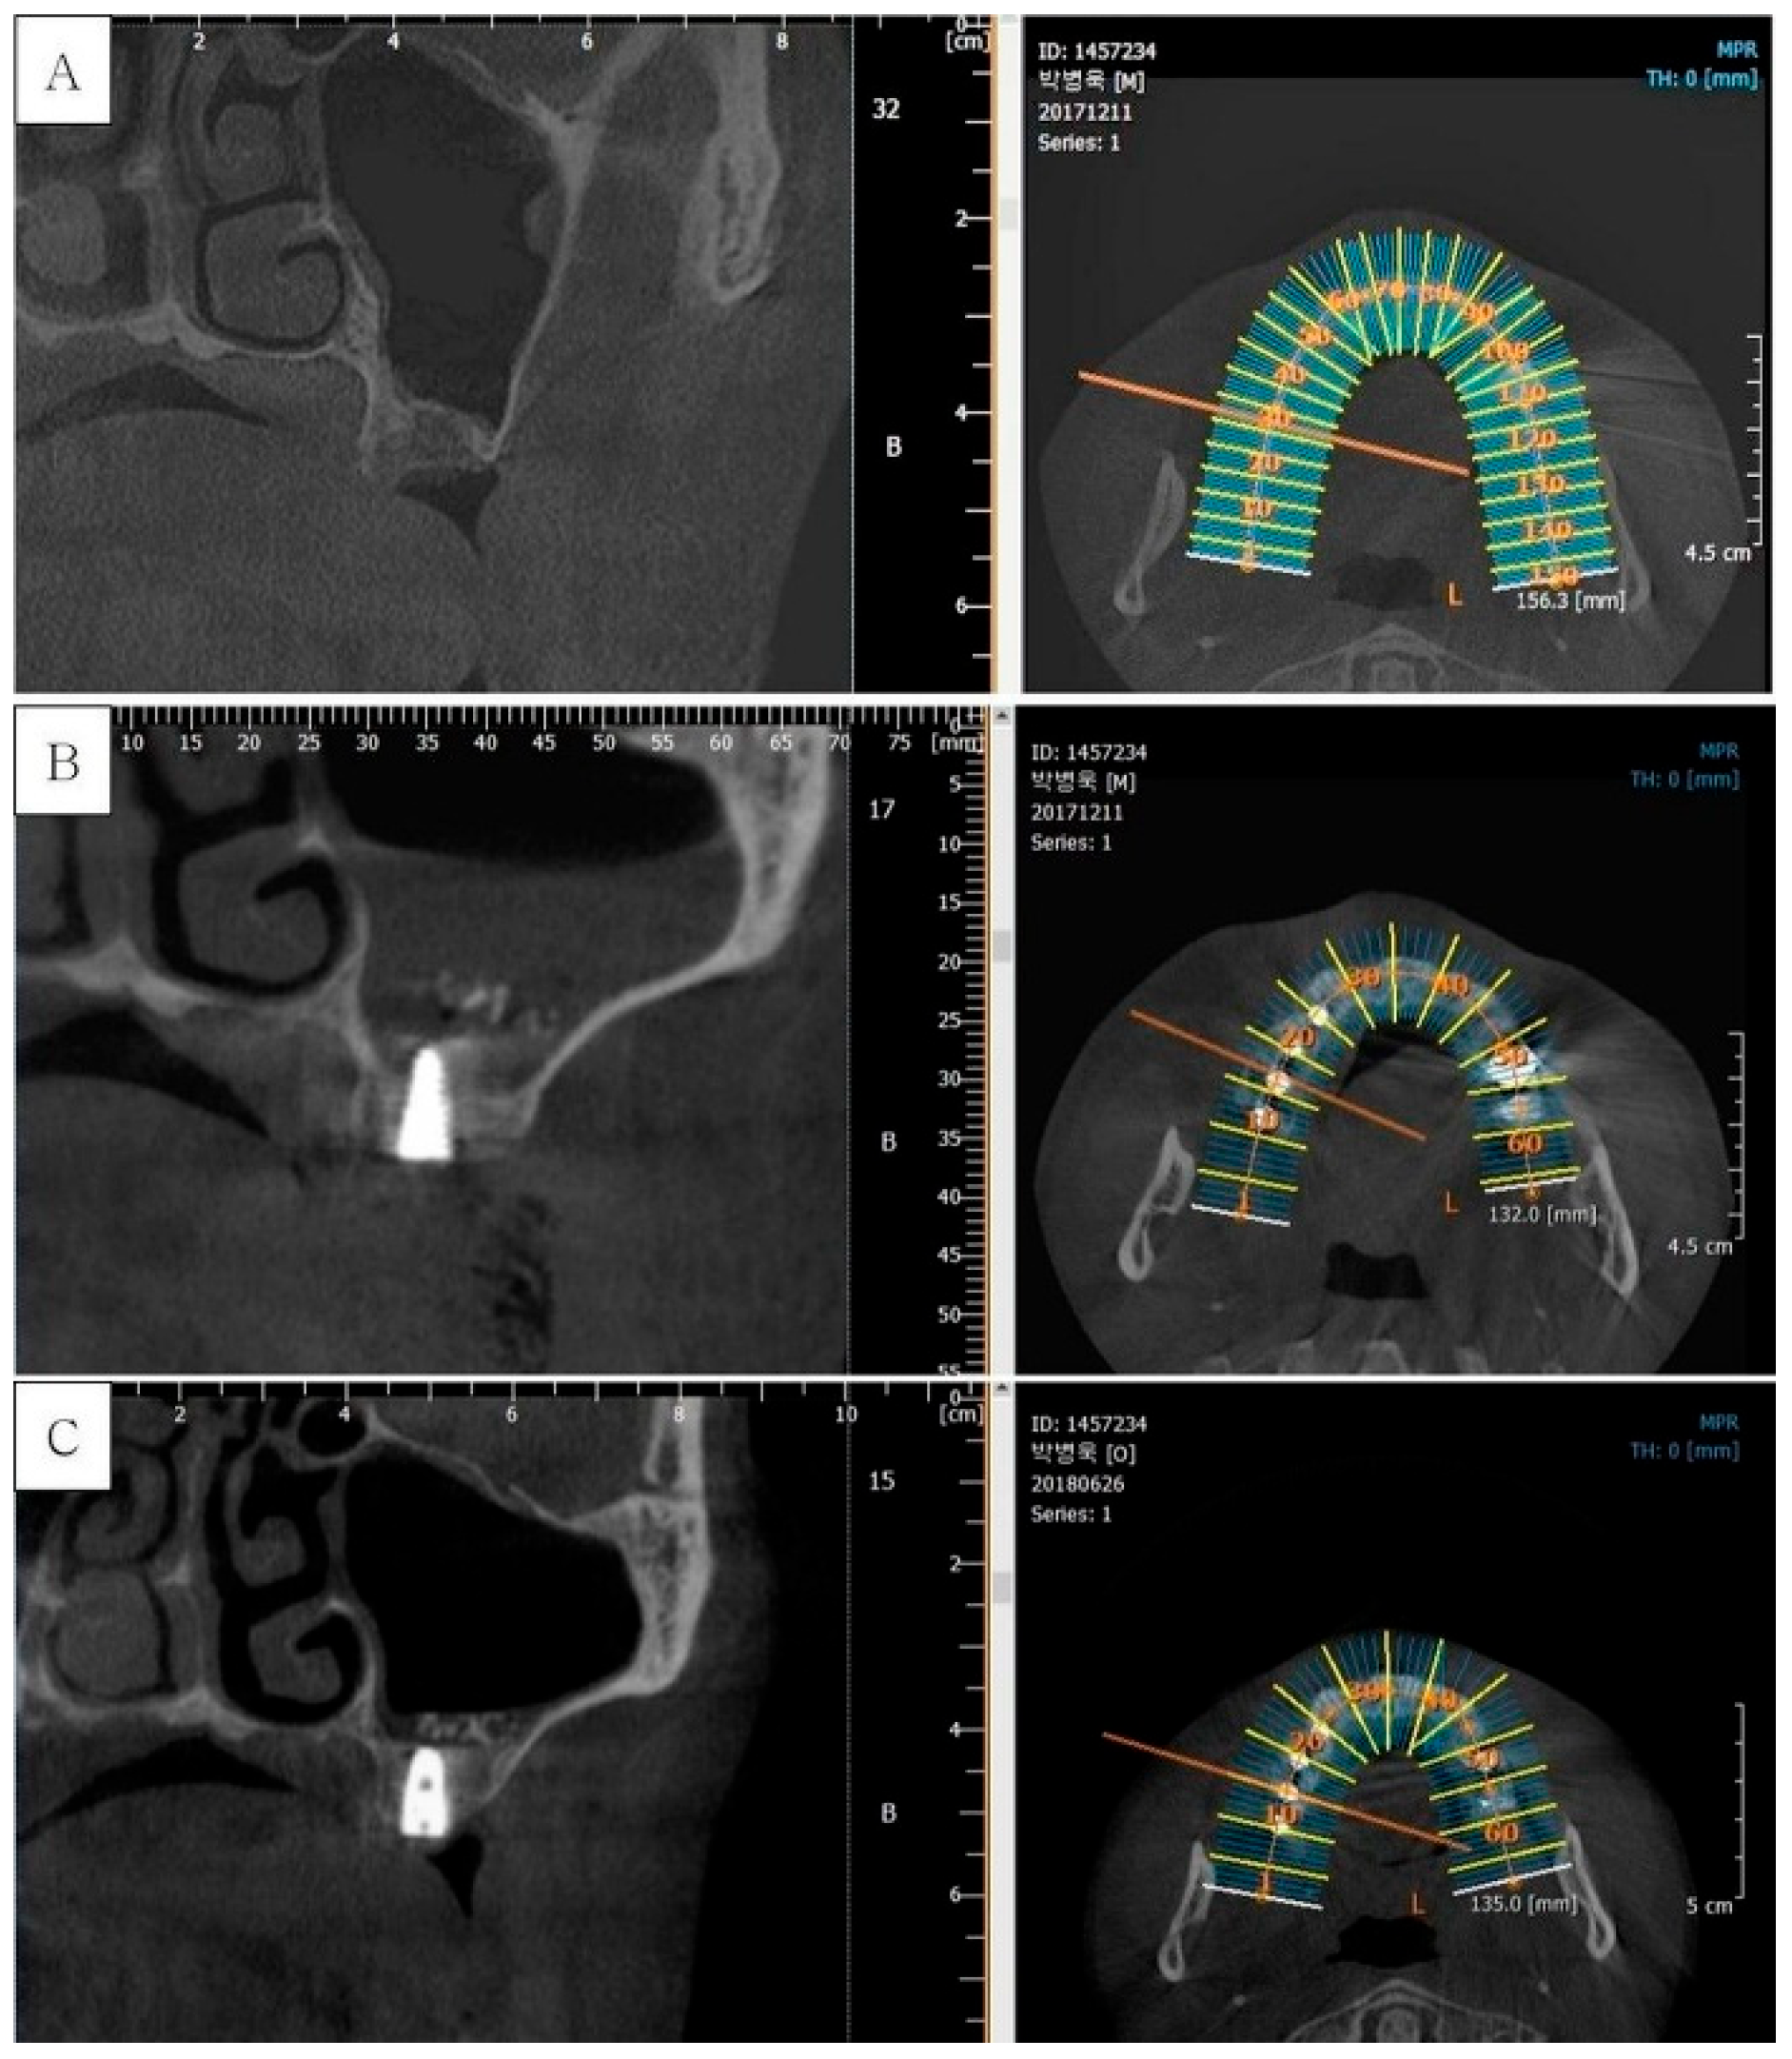

2.1. Patient Selection This retrospective study analyzed 18 patients who underwent implant treatment with maxillary sinus augmentation at the Department of Dentistry, Daegu Catholic University Hospital, Republic of Korea, between 2017 and 2022. The study was approved by the Institutional Review Board of Daegu Catholic University Medical Center (IRB Approval No. CR-22-174-L). Before surgery, all patients received an explanation of the procedure and provided written informed consent. Each patient’s medical history was thoroughly reviewed before inclusion, and individuals with conditions affecting bone metabolism were excluded. Smokers were not excluded from the study, but they were informed that smoking could negatively affect the implant and sinus augmentation procedure. All selected patients were free of surgical contraindications. The procedure was performed using a standardized surgical approach in the maxillary premolar and molar regions of partially or fully edentulous patients. Implant mobility was the primary criterion for determining implant failure, which was defined as the need for implant removal. The survival rate was evaluated based on the duration from implant placement to either the final follow-up or the occurrence of implant failure. Preoperative radiographic evaluations were conducted to analyze sinus conditions and residual bone height. Panoramic radiographs (Point HD; PointNix, Seoul, Korea) and cone beam computed tomography (CBCT) scans (ImplaGraphy; Vatech, Gyeonggi-do, Korea) were used for preoperative assessment and postoperative evaluation of bone gain. Residual bone height was measured in millimeters using dedicated software, and the maxillary sinus width was recorded at its broadest point. Since the Schneiderian membrane may collapse in the absence of tenting material, the extent of membrane elevation was determined by measuring the distance from the original sinus floor to the highest point of the grafted bone. 2.2. Preparation of Autogenous Tooth Block Bone Extracted maxillary premolar and molar teeth were converted into demineralized autogenous tooth block bone. The preparation involved sectioning the extracted tooth along its longitudinal axis using a disk, followed by the creation of multiple micro-holes with a round carbide bur to enhance blood penetration. The tooth block underwent demineralization for 30 min with 0.6 N hydrochloric acid in a vacuum-ultrasonic system (Vacua-Sonic System, CosmoBioMedicare Co., Seoul, Republic of Korea). Then, the tooth block was sterilized using a peracetic acid ethanol solution in a specialized device equipped with vacuum compression and ultrasonic vibration. After sterilization, the demineralized dentin-derived matrix particles were washed with phosphate-buffered saline (PBS), treated with a sterilization reagent, and rinsed with it, along with distilled water. 2.3. Surgical Protocol All patients followed the same pharmacologic protocol for prophylactic antibiotic administration. The routine prescription included amoxicillin sodium (Augmentin; Ilsung Pharmaceutical, Seoul, Korea) 500 mg, taken three times daily from one day before surgery until seven days after surgery. Additionally, a single intravenous dose of amoxicillin sodium (Amocla; Kunil Pharm, Seoul, Korea) 1 g was administered one hour before surgery. Local anesthesia was administered via a posterior superior alveolar nerve block using 2% lidocaine containing 1:100,000 epinephrine. The alveolar crest and the lateral wall of the maxillary sinus were uncovered by full-thickness mucoperiosteal flap reflection. To create the lateral window, a piezoelectric device (Surgybone; Silfradent, Sofia, Italy) equipped with a thin saw tip (S-Saw; Bukboo Dental, Daegu, Korea) was used under continuous saline irrigation (Figure 1A,B). The anterior vertical osteotomy line was positioned 3 mm posterior to the anterior sinus wall, while the distal osteotomy line was created approximately 15 mm posterior to the anterior vertical line. The vertical osteotomy height measured around 10 mm. The osteotomy design consisted of anterior and inferior cuts angled at 45° to the lateral sinus wall, whereas the superior and posterior osteotomies were made perpendicular to the lateral wall. This trapezoidal configuration facilitates repositioning the bony window to its original location after surgery (Figure 1C). The bony window was carefully separated from the maxillary sinus wall. The exposed Schneiderian membrane was then gently elevated using a flat sinus lift instrument (Figure 1D). The sinus membrane was continuously lifted until the medial and posterior walls of the maxillary sinus were exposed, after which implant placement was performed simultaneously (Figure 1E). The prepared demineralized autogenous tooth block bone was applied to the space between the apex of the placed implant and the elevated Schneiderian membrane. This helps to maintain the Schneiderian membrane elevation (Figure 1F). The bony window, once detached from the sinus wall, was repositioned to its original location. The process helps prevent soft tissue infiltration into the sinus space and promotes new bone formation (Figure 1G). Polytetrafluoroethylene sutures (Cytoplast; Osteogenics Biomedical, Lubbock, TX, USA) were used to suture the flaps with a combination of continuous locking and interrupted suturing techniques to ensure passive primary closure (Figure 1H). Postoperative instructions included avoiding nose blowing for two weeks and preventing forceful sneezing or coughing with a closed mouth. Antibiotic prophylaxis continued for one week postoperatively, and sutures were removed two weeks after surgery. After surgery, panoramic radiographs and dental cone beam computed tomography (CBCT) scans were taken to assess the surgical procedure. A healing period of 6 to 8 months was observed for osseointegration before the second-stage procedure. Before this phase, additional CBCT scans were performed (Figure 2).

3.1. Clinical Results A total of 18 patients (11 males and 7 females) with a mean age of 53.7 years participated in this study, and all patients attended follow-up visits without any dropouts. Sinus augmentation was performed bilaterally in one patient and unilaterally in 17 patients, resulting in a total of 19 Schneiderian membrane elevation procedures and 25 implant placements. During the follow-up period, apart from mild swelling at the surgical site during the early postoperative phase, no significant complications were reported. Additionally, none of the patients exhibited an infection or sinus-related disease. Schneiderian membrane perforations, each measuring less than 3 mm, were encountered in three cases during the sinus elevation procedure. These perforations were successfully managed using absorbable collagen material (CollaTape; Zimmer Dental, Carlsbad, CA, USA). The overall implant survival rate was 100%, with no instances of implant mobility throughout the study. These findings suggest that minor Schneiderian membrane perforations had no adverse impact on clinical outcomes. 3.2. Radiographic Results Radiographic evaluation in this study consistently demonstrated a significant increase in alveolar bone height and stable new bone formation around implants following sinus augmentation with demineralized autogenous tooth block bone (Figure 3). Notably, the newly formed bone maintained its height and density during the follow-up period, with no evidence of marginal bone loss or sinus pathology on panoramic and CBCT images. These findings suggest that the tooth block graft provided effective space maintenance and osteoconductive support, likely due to its physical stability and biological compatibility. Importantly, the data revealed a positive correlation between the extent of Schneiderian membrane elevation and the amount of new bone formation, while preoperative bone height and sinus width did not significantly affect bone gain (Figure 4), (Table 1). This indicates that, within the study’s parameters, the success of bone regeneration was more closely related to the surgical elevation achieved than to initial anatomical limitations. The absence of radiographic complications such as sinusitis or graft resorption further supports the safety and predictability of this approach. These radiographic outcomes are in line with previous studies, which have shown that autogenous tooth-derived grafts can provide both structural support and biological stimulation for bone regeneration. Radiographic assessment of the maxillary sinus and alveolar crest.